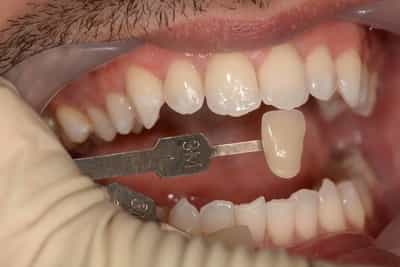

Eclaircissement Dentaire ou Blanchiment

L’éclaircissement dentaire est une technique consistant à rendre aux dents une couleur plus harmonieuse, plus en adéquation avec l’image que le patient veut donner de lui. Le blanc des yeux est une référence. A l’échelle du visage, la blancheur de la sclérotique de l’oeil (blanc des yeux) fait ressortir la couleur jaune des dents. Pour une meilleure harmonie, il faut aligner ces deux couleurs. Si les dents sont moins lumineuses, l’éclaircissement va améliorer l’apparence. Après éclaircissement, cette différence s’atténuera et donnera une harmonie du visage.

Souvent, à partir d’un certain âge, les dents changent de couleurs. Ces changements peuvent être dûs à des colorations extrinsèques. Dans ces cas, un simple nettoyage-polissage peut suffire à y remédier.

Dans d’autres cas, il s’agit d’une usure de l’émail. L’émail est responsable de la luminosité de la dent, et son usure a tendance à révéler la couleur de la dentine sous-jacente. Elle peut être marron, jaune, grise, orange… L’éclaircissement agit sur les colorations intrinsèques et extrinsèques, en surface et en profondeur.

-le blanchiment externe : il concerne les dents vivantes et consiste à l’application d’un gel éclaircissant sur l’extérieur des surfaces dentaires. Cette technique de homebleaching nécessite obligatoirement l’accompagnement de votre dentiste. Il faut savoir gérer les éventuelles sensibilités pouvant apparaitre dans de rares cas. Le blanchiment doit être encadré dans son protocole et sur toute sa durée.